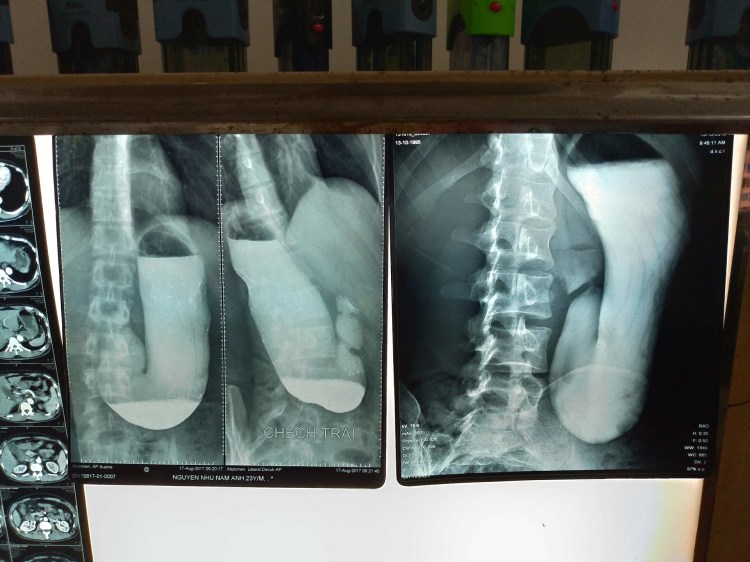

胃部レントゲン(バリウム検査)とは、通常のX-Rayと少し違くて、レントゲンを撮る前に、めちゃくちゃ苦い発泡剤(バリウム)を飲まないといけませんでした。この発泡剤を飲むと、レントゲンで口から食道、胃、十二指腸へと流れていく様子をみることができます。

そこで、こちらが結果

左側の写真は去年の9月に撮ったものです。そして、今回の写真(右側)と比べると、確か、胃が前より下に落ちているような感じ…結構グロいですね。これが胃下垂です。胃が通常の位置から落ちている症状。まあでも、右側の写真の方がズームされているので、実はそんなに変わっていないと思います。あと、ななめに立っていたので、胃が曲がっていました。通常の元気な胃は、満腹になったときは縦ではなく、横に伸びます。ちなみに、血液検査の結果は問題なかったです。